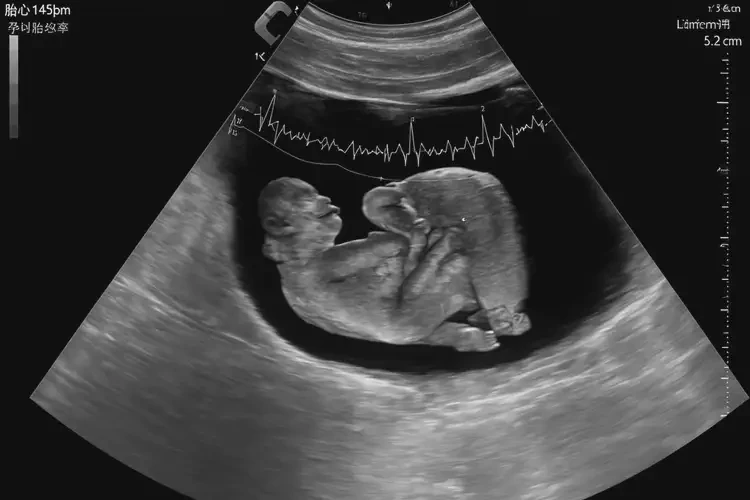

孕19周4天胎心率93還要保胎嗎(圖1)

• 超聲檢查:觀察胎兒的生長(zhǎng)發(fā)育情況、胎盤和臍帶狀況等。